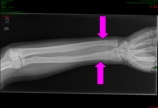

【骨质疏松】骨质疏松骨折病例分享

病情概述: 性别:女年龄:32岁体重:61Kg;右前臂外伤后疼痛伴功能障碍1小时,患者于1小时前进地铁车厢时右前臂不慎被车门夹伤,即刻疼痛伴功能障碍,来我院急诊就诊。拍摄X片示右前臂尺桡骨干双骨折。否认有骨折史,否认有其他系统性疾病,否认检查过骨密度,否认检… [详情]